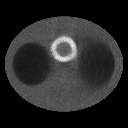

As expected, the images by the superiorized EM algorithms

are superior to the one by the classic EM algorithm in terms of TV value, -norm and RMSE

(see figure 3 and table 1), though the images by the superiorized algorithm 1 are

visually indistinguishable from the one by the classic EM algorithm.

Furthermore, the superiorized EM algorithm 2 are superior to the

superiorized EM algorithm 1,

because the regularization parameter goes to zero very fast for the superiorized EM algorithm 1.